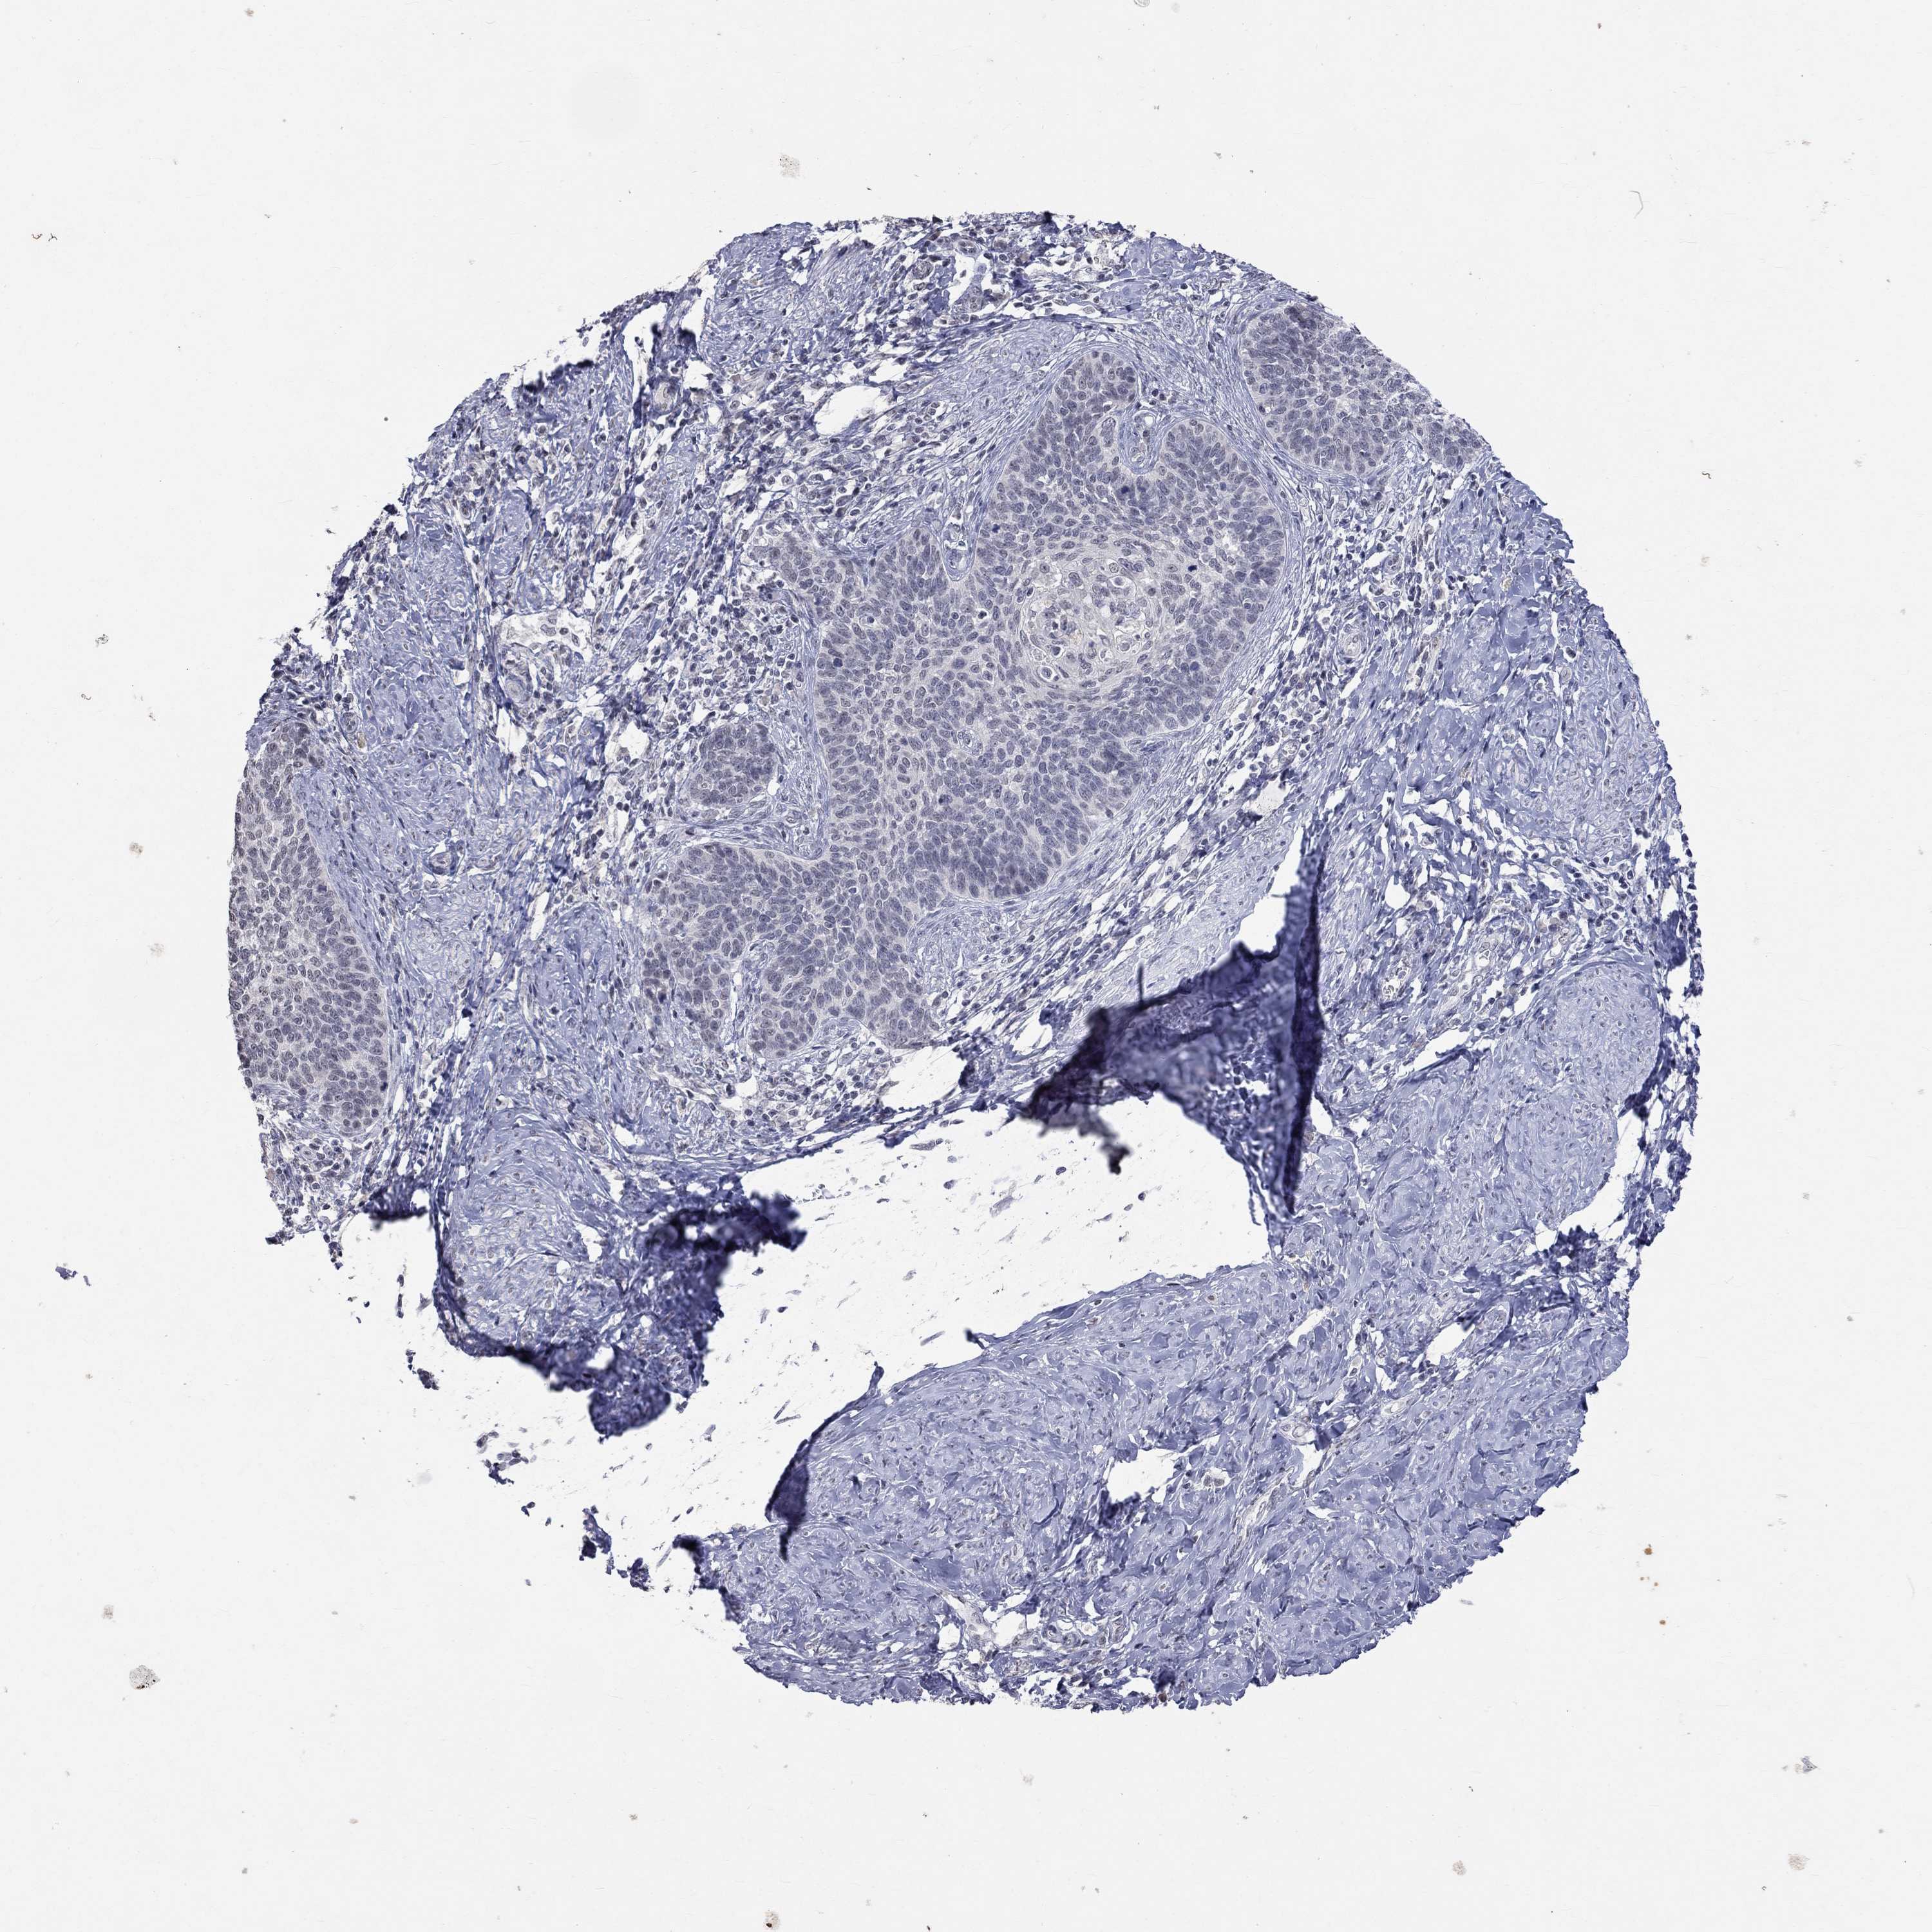

CERVICAL CANCER - Protein expressioni

A mouse-over function shows sample information and annotation data. Click on an image to view it in a full screen mode. Samples can be filtered based on level of antibody staining by selecting one or several of the following categories: high, medium, low and not detected. The assay and annotation is described here.

Note that samples used for immunohistochemistry by the Human Protein Atlas do not correspond to samples in the TCGA dataset.

Antibody stainingi

Antibody staining in the annotated cell types in the current human tissue is reported as not detected, low, medium, or high, based on conventional immunohistochemistry profiling in selected tissues. This score is based on the combination of the staining intensity and fraction of stained cells.

Each image is clickable and will lead to virtual microscopy that enables deeper exploration of all samples and also displays staining intensity scores, fraction scores and subcellular localization as well as patient and tissue information for each sample.

Antibody HPA014476

Antibody HPA058645

Staining

High

Medium

Low

Not detected

Intensity

Strong

Moderate

Weak

Negative

Quantity

>75%

75%-25%

<25%

None

Location

Nuclear

Cytoplasmic/membranous

Cytoplasmic/membranous,nuclear

Squamous cell carcinoma, NOS

Adenocarcinoma, NOS